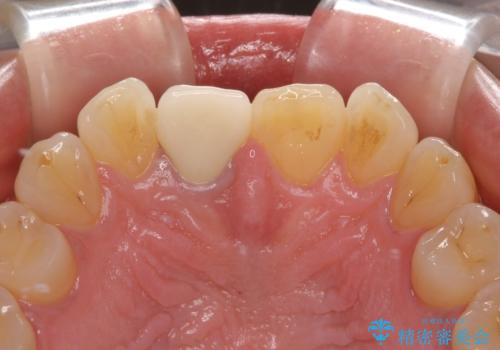

奥歯は虫歯が放置されていましたが、特に症状はなく歯髄の状態も正常でした。

前歯、奥歯ともにオールセラミッククラウンやセラミックインレーにて治療を行うこととしました。

前歯のセラミッククラウンは周りの歯と調和させるためにオーダーメイドタイプのものをおすすめしましたが、元が白すぎていたため、概ね色合いが合えば大丈夫であるとのことで、既製パターンの色調で仕上げました。